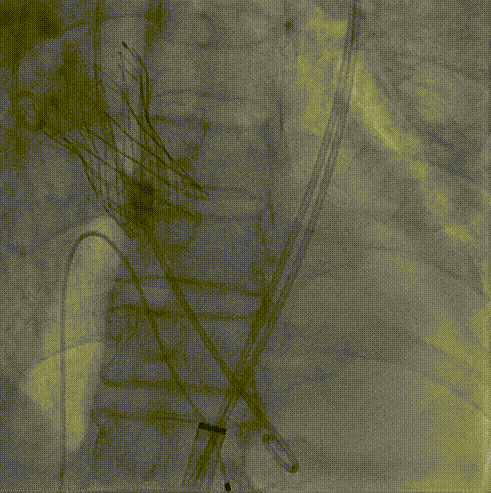

3.TaurusElite AV26号瓣膜定位及释放。瓣膜初始定位0位,开花后120次起搏,释放到工作位后造影显示瓣膜位置较深,形态敞口状,预估释放后存在进一步下滑风险,决定回收调整。

第一次瓣膜初始定位

第一次工作位造影

4.瓣膜第一次释放下滑明显,第二次初始定位瓣上2mm,缓慢释放开花,提拉输送器,快速释放到工作位,造影显示位置良好,少量瓣周漏,决定脱钩

第二次瓣膜初始定位及释放

第二次瓣膜脱钩